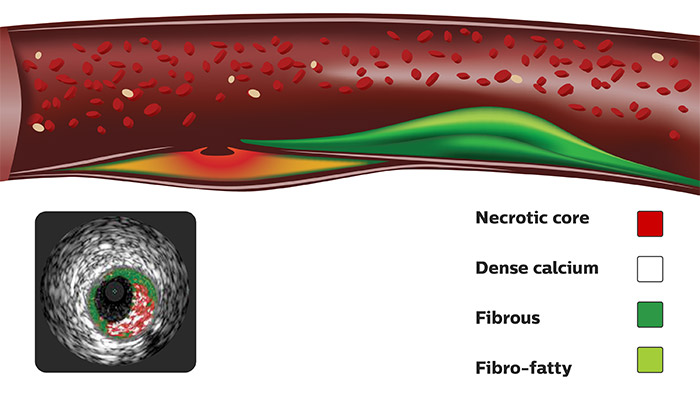

VH IVUS imaging provides a colorized tissue map of plaque composition with automated lumen and vessel measurements.* VH IVUS technology uses advanced, proprietary spectral analysis techniques to classify plaque into four tissue types with 93-97% accuracy.1

For complete lesion assessment, VH IVUS provides a colorized tissue map of four tissue types:

For a simplified view, VH IVUS features an alternate option to display only necrotic core and dense calcium.